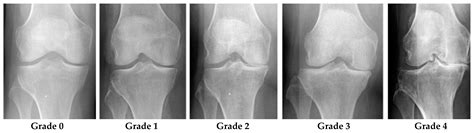

• Healthy Joint Space: The gap between the bones, which is normally filled by cartilage, appears to be of a healthy, expected width, suggesting that there is not severe, advanced osteoarthritis.

Bone Yes Fractures, bone spurs, severe arthritis

Cartilage Indirectly (via space) Meniscus tears, chondromalacia

• Early-Stage Arthritis: While severe arthritis shows up as a narrowed joint space on an X-ray, very early stage cartilage wear may not be visible.